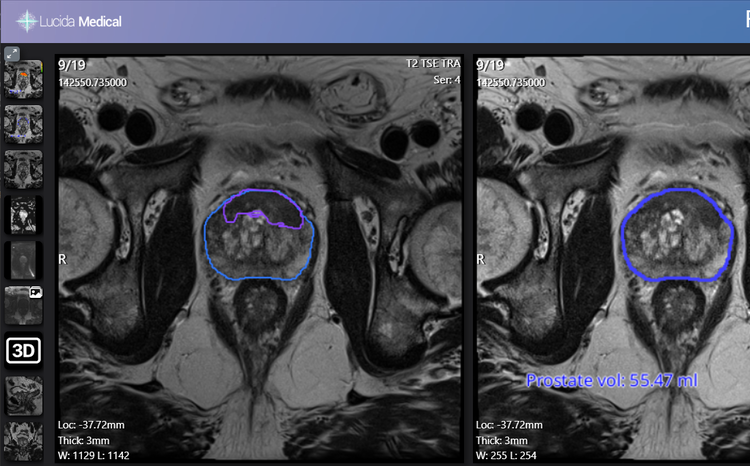

- Leeds Teaching Hospitals NHS Trust is piloting an AI tool for prostate cancer diagnosis, designed by Lucida Medical

- The trust is testing whether the Prostate Intelligence (Pi) tool can accurately identify prostate cancer based on MRI scans

The one-month pilot, which began in August 2024, is testing the effectiveness of the Prostate Intelligence (Pi) tool, an advanced AI and machine learning software system, in detecting prostate cancer lesions from magnetic resonance imaging (MRI) scans.

Pi assists radiologists by using AI algorithms to analyse prostate MRI images, highlight potential areas of concern and assess risk scores and prostate size, which can impact biopsy and treatment decisions.